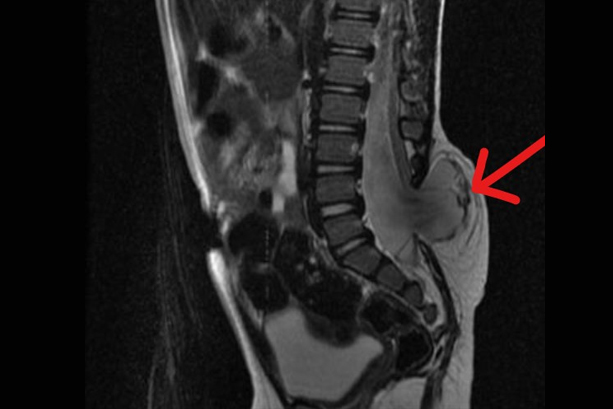

SRF TAKES PRIDE IN PRESENTING TO YOU A FEW INTERESTING CASES

More than 300 Underprivileged Patients have been Operated through our Foundation over the last 15 years !

book_4 Notable

Cases